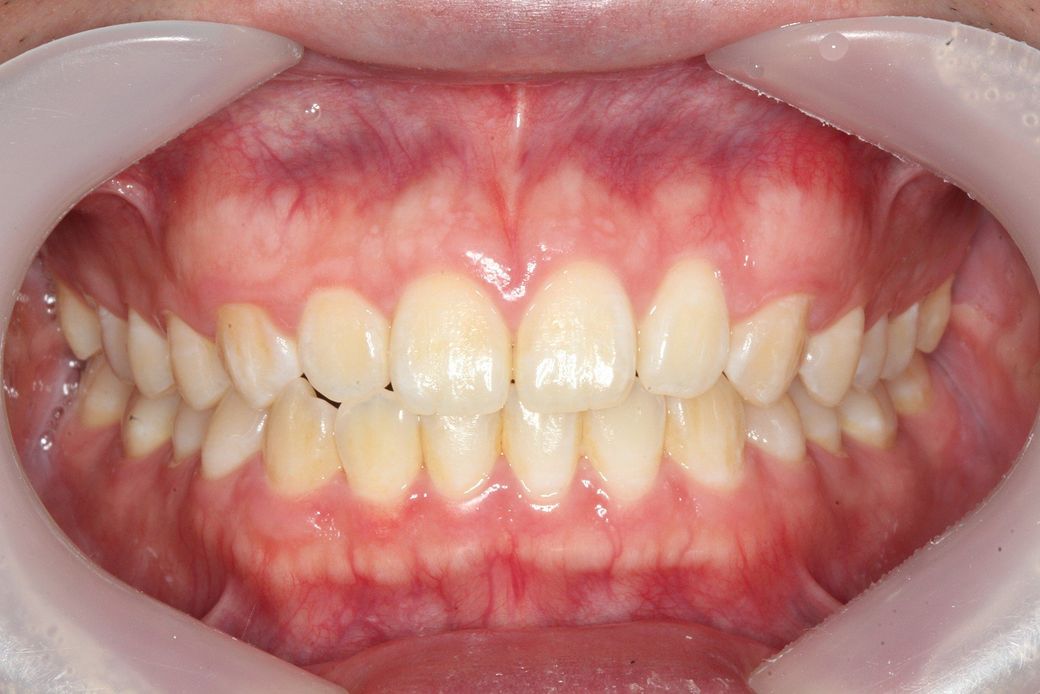

• 3번 째 사진

3. 현재 턱이 좌측으로 canting 되어 있는 상태이기는 하나 외관상 크게 비대칭으로 보이지 않는다면 수술이나 교정의 대상이 아닙니다. 비대칭은 반드시 치료를 하는 것이 아니고 환자가 필요하다면 치료를 하게 됩니다. 즉 환자가 심미적으로 비대칭이라도 크게 문제를 느끼지 않는다면 병적 상태( 턱관절염)을 제외하고는 치료하지 않습니다.